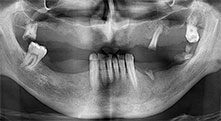

Bratu: We routinely use the instruments for harvesting bone blocks and splitting alveolar ridges. We also use the Piezomed B6/B7 for osteotomy of impacted teeth and removing failed implants. All indications that require deep, clean cuts.

Bratu: We prefer to harvest bone from the external oblique ridge of the posterior mandible, not from the interforaminal region. After the soft-tissue incision, we use the new saws to define the amount of bone to harvest. With this approach, we also use them for the entire preparation in almost 80% of cases. We may also use other piezo instruments and then at the end a chisel to mobilize the block. We find that this is a very effective surgical technique.

Bratu: I consider piezo surgery a great leap forward in oral surgery. The technique makes bone preparation safer and easier. Little bone is lost, for example in extractions. This is very important in the aesthetic zone, particularly if immediate implantation is planned. Piezo surgery is also safer for soft tissue: injuries to membranes in the sinus are basically history, as are nerve injuries when bone blocks are being harvested. Data indicating reduced postoperative swelling and pain are also available. Piezo surgery is also ideal for preparation of sinus septa. And last but not least, our patients benefit from the atraumatic nature of this technology.